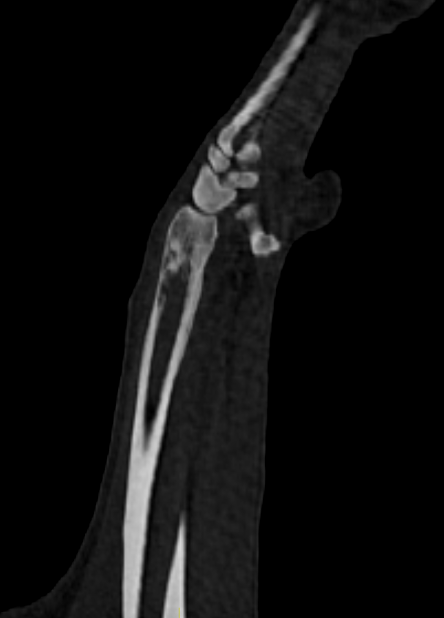

Strahlentherapie bei Bruno

Glück im Unglück: Brunos Besitzer:innen haben die Probleme sehr früh erkannt und die Diagnostik wurde sehr zügig durchgeführt. So zeigte sich der Knochen ausreichend stabil für eine stereotaktische Strahlentherapie, eine Amputation lehnten die Besitzer nach ausführlicher Aufklärung ab. Der erste Termin dient hier neben der Vorbesprechung und Aufklärung vor allem der Anfertigung einer Computertomographie zur Bestrahlungsplanung. Da bislang keine CT vorlag wurde auch ein Thorax-CT zur Metastasensuche angefertigt, welche glücklicherweise negativ war. Bruno wurde in drei Fraktionen bestrahlt und auch er hat die Narkosen erwartungsgemäß gut vertragen. Innerhalb der ersten drei wöchentlichen Follow-Ups berichteten die Besitzer bereits von einer moderaten Schmerzreduktion. In Summe muss man diese natürlich als Kombination aus Strahlentherapie und medikamentöser Therapie sehen; Bruno erhielt ein Amantadin-Derivat, Gabapentin und ein NSAID als Kombinationstherapie. Eine Chemotherapie wurde seitens der Radioonkologie angeraten, zur entsprechenden Beratung erfolgte eine Rücküberweisung an die erstbehandelnde Tierklinik. Nach umfassender Aufklärung entschieden sich die Besitzer:innen ganz bewusst gegen eine Chemotherapie. Die Problematik der kontaminierten Ausscheidungen hätte umfassende Einschränkungen in Brunos Alltag als Hofhund bedeutet. Viele Freiheiten und seine umfassende Selbstständigkeit wären nicht mehr möglich gewesen, was für die Halter:innen keine Option war. Acht Monate nach Ende der Strahlentherapie ist Bruno mit Begeisterung in den Weinbergen unterwegs und kümmert sich weiter pflichtbewusst um den Hof.